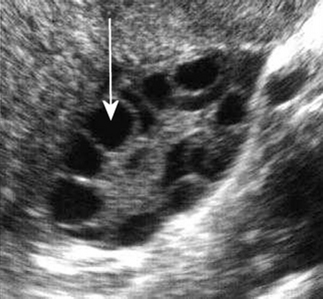

The process of reflection of sound at a boundary is illustrated in Figure 42.3. Dense objects such as gallstones reflect back large amounts of sound, due to the large acoustic impedance difference between themselves and surrounding substances. This may lead to the appearance of an acoustic shadow on an ultrasound scan. This takes the form of a dark echo-free band radiating out behind the stone, in a region where no sound has penetrated. An acoustic shadow can be seen in Figure 42.4.

Figure 42.4 A gallstone (white arrow) is returning many echoes and has a bright hyperechoic appearance on its leading face. Behind this there is an acoustic shadow (black arrow) where no sound has been transmitted. There are also bright echoes at the boundary between the wall of the gall bladder and its contained fluid, which appears dark and anechoic (star).